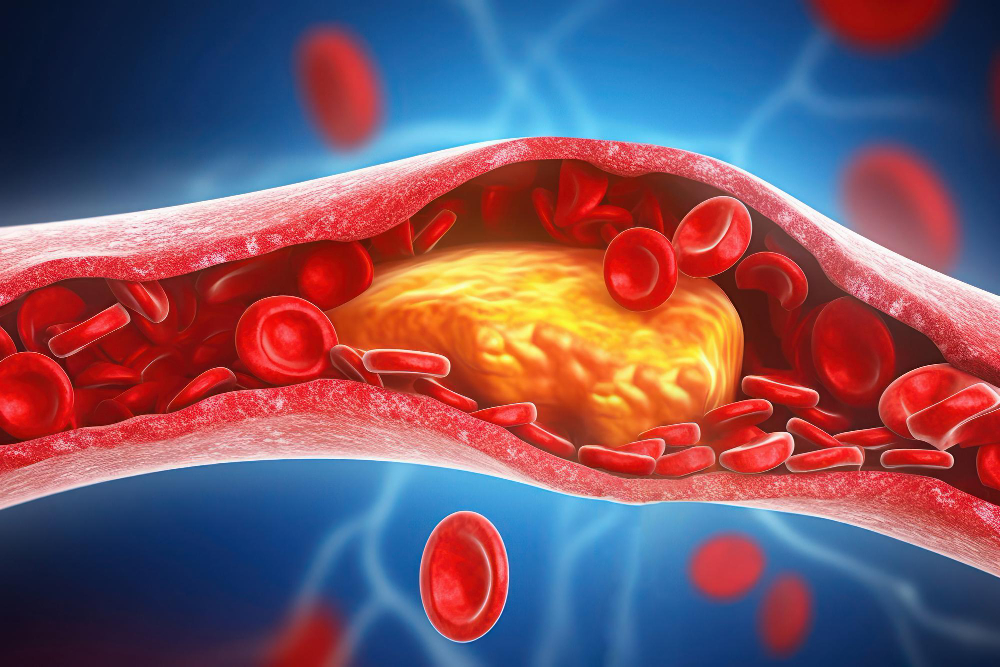

What is a Heart Attack? A heart attack happens when blood flow to part of the heart muscle gets blocked. Because the heart needs oxygen-rich

What is Dyslipidemia? Dyslipidemia means your blood has unhealthy levels of fats, such as cholesterol or triglycerides. These fats are important, but too much can